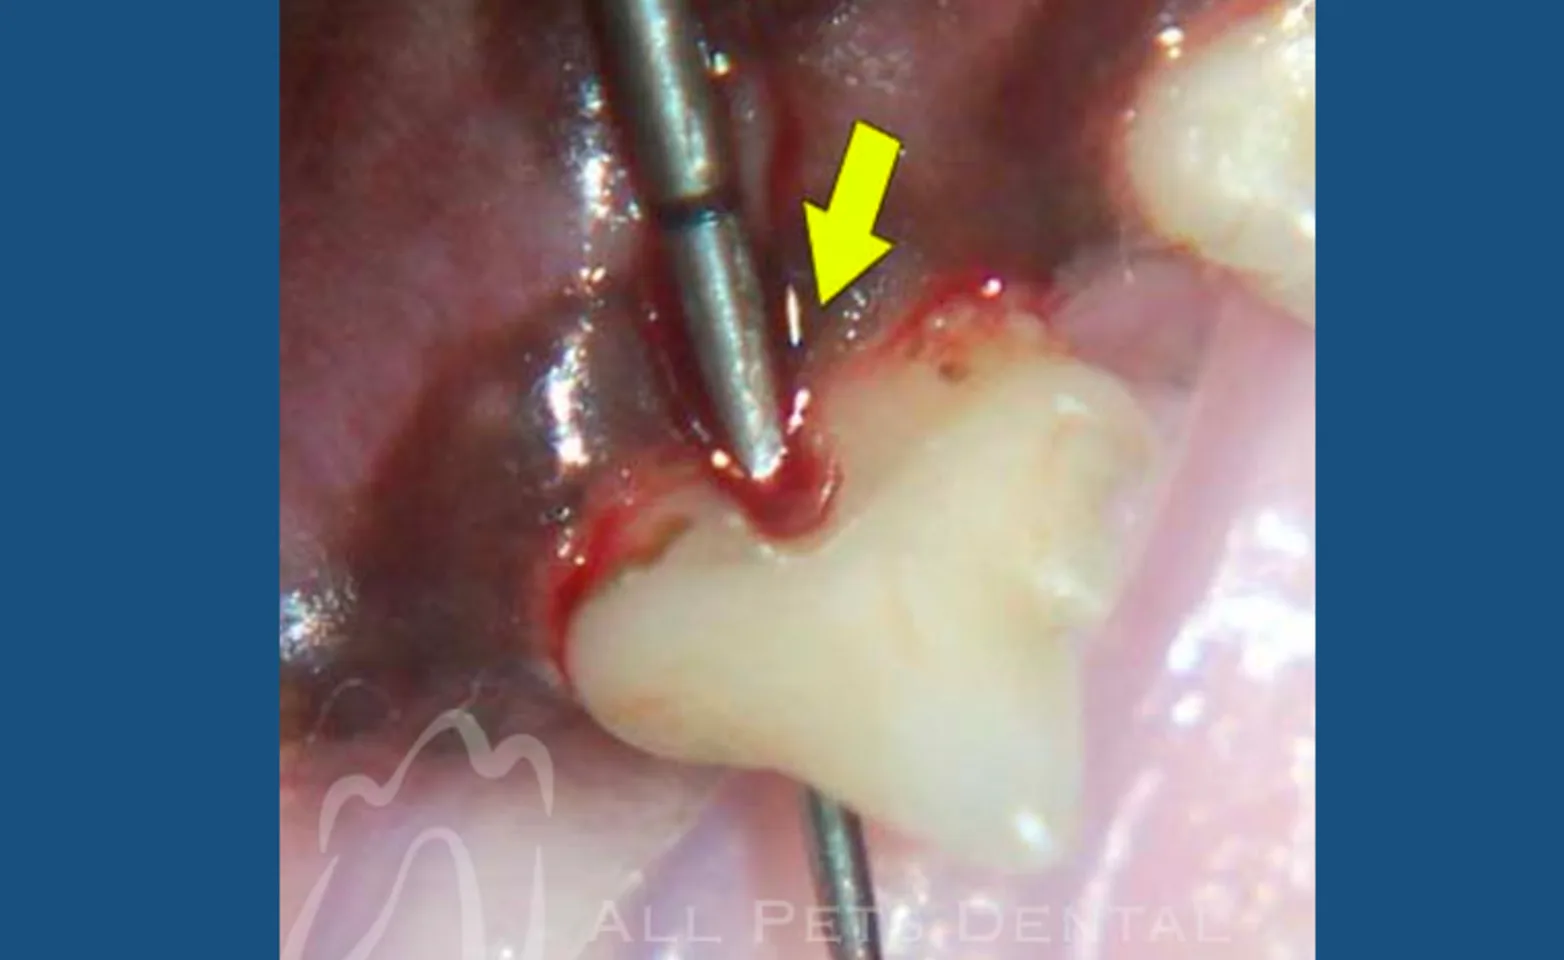

Furcation Exposure

Established and advanced periodontal disease can result in loss of bone support where the roots of multi-rooted teeth meet. Once furcation exposure has occurred, tooth extraction is the treatment of choice.